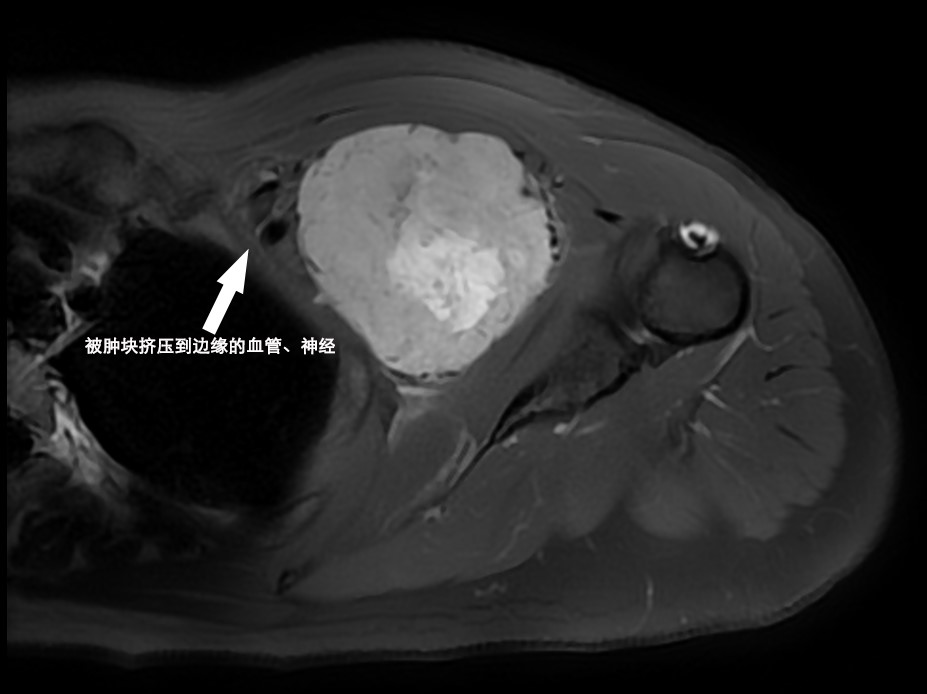

近日,我院血管外科与介入科完成一例侵犯左锁骨下血管及臂丛神经的罕见肿瘤切除。家住园区的王女士最近感觉左臂时常有麻木感,遂到我院就诊。接诊医师发现王女士左肩部前方明显隆起“疙瘩”,于是建议其做了左肩部的MRI检查。结果出来后,接诊医师惊讶地发现在她的左锁骨深面胸壁上有一个“鸭梨”大的肿块,肿块将左锁骨下血管、臂丛神经等紧密粘连在一起,这正是王女士时常感到手臂麻木的原因。

因为肿块和血管、神经的关系紧密,接诊医师建议她到血管外科与介入科就诊。为了明确肿块的性质,确定手术预案,程龙副主任医师先在彩超引导下用一根很细的穿刺针从肿块内部取出了一条肿块组织进行病理检查。两天后,病理报告提示为孤立性纤维瘤。这是一种比较罕见的肿瘤,而且有一定的恶性比例,这也就意味着手术必须完全切除肿瘤,如果残留一点都可能导致术后的复发、转移。以张喜成主任为首的几位血管外科专家在术前与相关科室多次探讨了手术方案,若要切除该肿瘤,它与周围重要血管神经的紧密粘连便是一项“大考验”!既要把肿瘤切干净,又要保护血管神经,否则可能会导致左上肢残疾。必要时可能还需要准备同时做人工血管移植,其中的难度可想而知。于是,他们就围手术期管理,麻醉术中的监护、术后的治疗等拟定了详尽的手术方案。